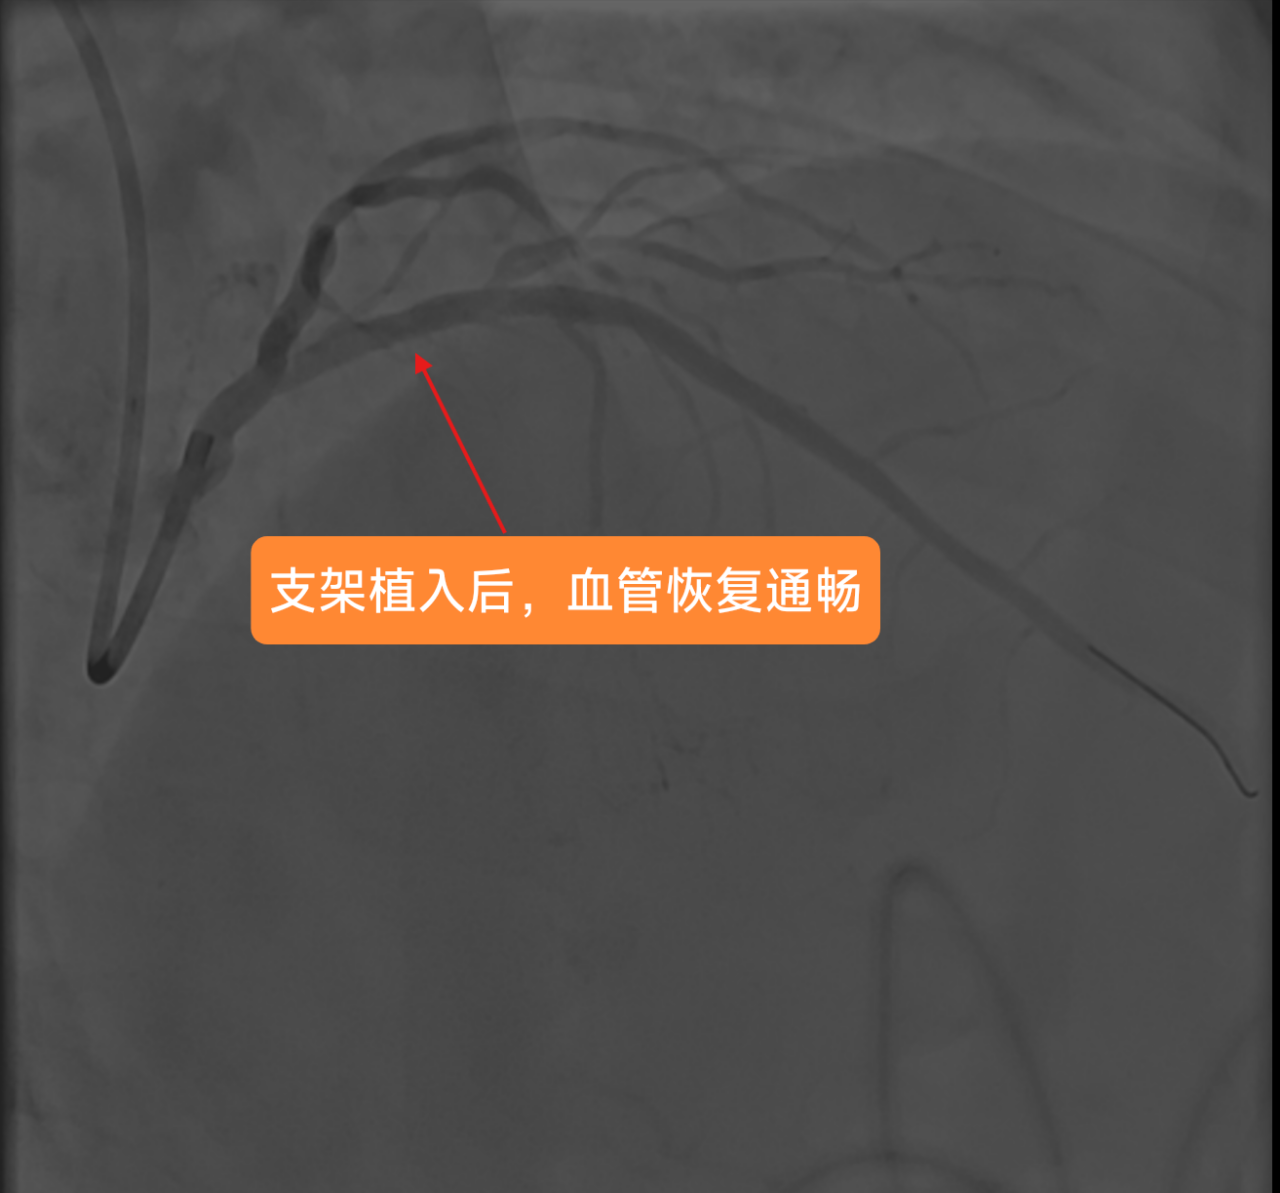

在征得家属同意后,医疗团队优先为罗先生实施心血管手术。然而,就在准备植入支架的紧要关头,患者突发室颤导致心跳骤停。经验丰富的手术团队临危不乱,立即启动应急预案,果断实施胸外按压,并给予两次精准电击除颤。在惊心动魄的几分钟后,罗先生的心脏终于恢复搏动。稳住患者生命体征后,玉溪市中山医院心内科业务主任李驹凭借精湛的医术,精准、迅速地将支架植入堵塞血管。随着支架成功撑开,停滞的血流瞬间恢复通畅,罗先生的心脏危机暂时得以化解。

支架植入后,患者前降支血管血流恢复通畅